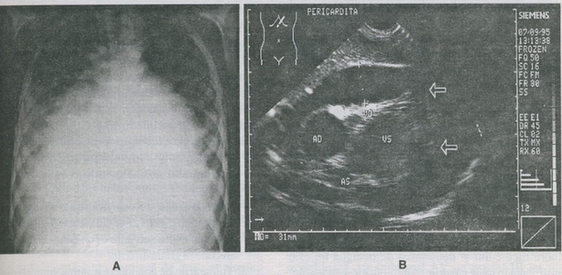

Fig. 9-18. Pericardita exsudativa la o fetita īn vārsta de 12 ani.

A. Radiografia cardiopulmonara arata silueta cardiaca mult marita de volum, unghiuri cardiofrenice obtuze, congestie vasculara pulmonara.

B. Echocardiografie 2-D evidentiaza zona sonotransparenta (sagetile) īn jurul ecoului cordului, care denota o mare cantitate de exsudat īn sacul pericardic.